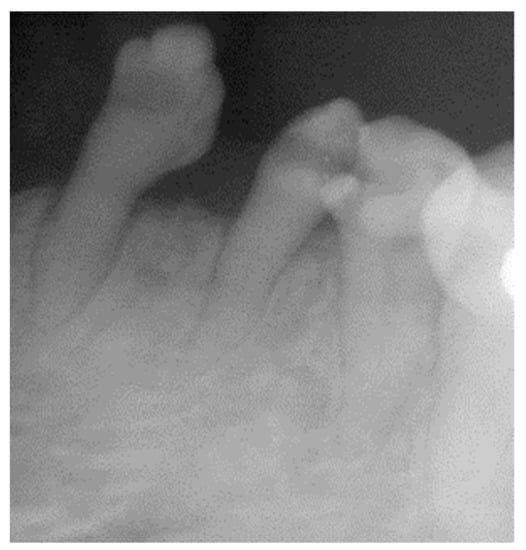

2.1. Clinical and Radiological Examination

- Pre-prosthetic care: exodontia, endodontic and restorative treatments were performed under general anesthesia. The following procedures were performed: endodontic treatment and bonded amalgam restorations for overdenture abutments of teeth numbers 11, 14, 15, 21, 24, 25 and 45 and exodontia of 46, 44, 43, 41, 33, 34, 35, 23, 22, 13 and 12 (Figure 6). The TRPD were placed on the day of surgery and a postoperative consultation was performed the following day to evaluate and adjust the prostheses (Figure 7).